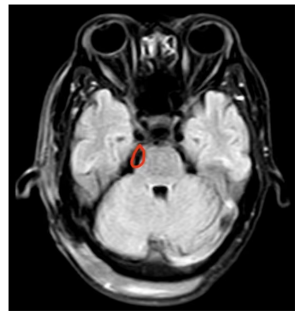

经过周密的术前准备,以神经外科副主任、主任医师樊天禹、副主任医师王红鑫为主的手术团队为患者进行了颅内肿瘤切除术。术中发现患者的肿瘤已侵犯多处脑神经,三叉神经受压尤其严重,肿瘤与周围组织黏连严重,且有多处血管阻断了手术视野,手术难度加大,稍有不慎将会导致严重的神经功能障碍,甚至危及患者生命。手术团队沉着应对,经过仔细辨认、耐心分离,历时3小时,肿瘤被全部切除,手术顺利结束。术后,王越醒来后感觉脸部疼痛消失,医生详细检查确认无面瘫等神经功能障碍。复查核磁共振,影像显示肿瘤切除干净,病检报告提示为颅内胆脂瘤,为良性肿瘤。

术后核磁共振影像结果显示肿瘤切除干净